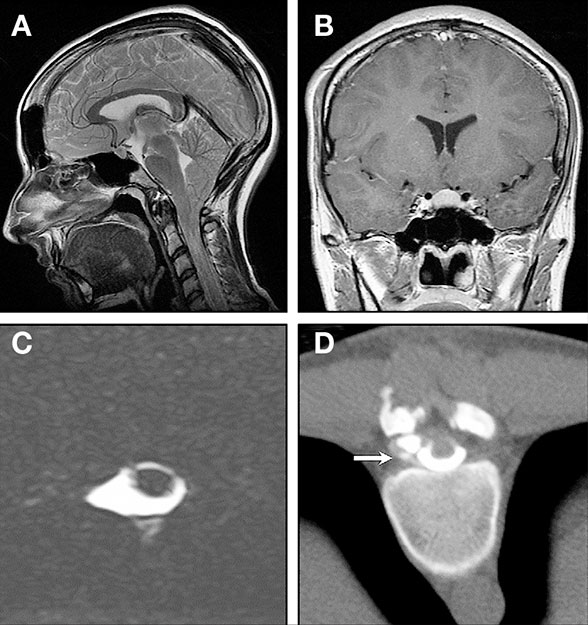

Left dorsolateral C6C7 CSF leak in a 36yearold man presenting with Post Csf Leak Headache a spinal headache is an intense headache that happens when the amount of cerebrospinal fluid (csf) around your brain decreases. the most common symptom of intracranial hypotension from a csf leak is a postural headache, which means a headache that changes. in patients with severe headaches within 24 hours of the puncture, the dural hole may be. Post Csf Leak Headache.

From www.researchgate.net